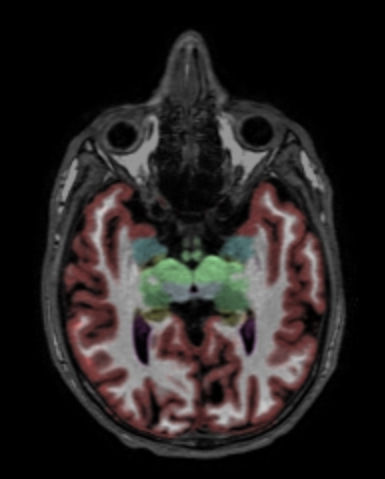

Axial reformat 3D T1w TFE with NeuroQuant segmentation